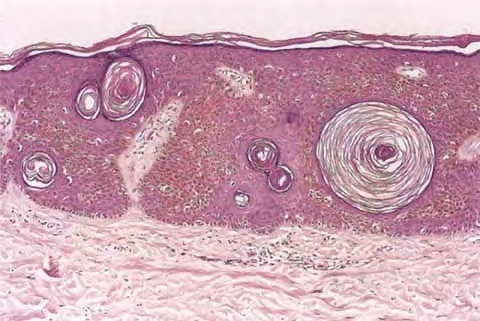

Seborrheic keratoses = التقران الدهني